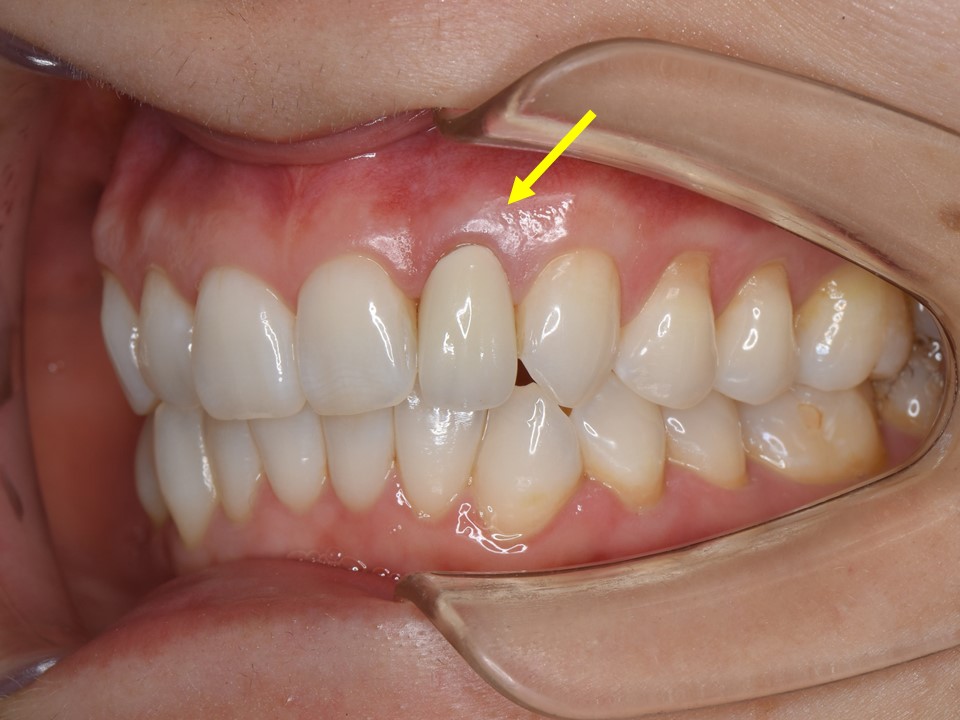

初診時口腔内。左側側切歯(⇒)のブラックマージンを主訴に来院。セラミッククラウンの色も透明感が無く、審美的な改善を希望。

装着してあるセラミッククラウンが不適合のため、歯茎に炎症を認める。